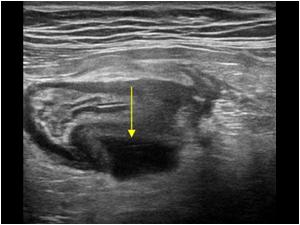

- Complicated diverticulitis: Intramural/pericolic abscess seen as an anechoic collection of air/debris

“Sonographic features of complicated diverticulitis: the images show the presence of diveticula, thickening of the bowel wall and pericolic fluid (a,b)”

Source: https://theultrasoundjournal.springeropen.com/articles/10.1186/2036-7902-5-S1-S5

Mural abscess

Source: https://www.ultrasoundcases.info/diverticulosis---diverticulitis-6835/